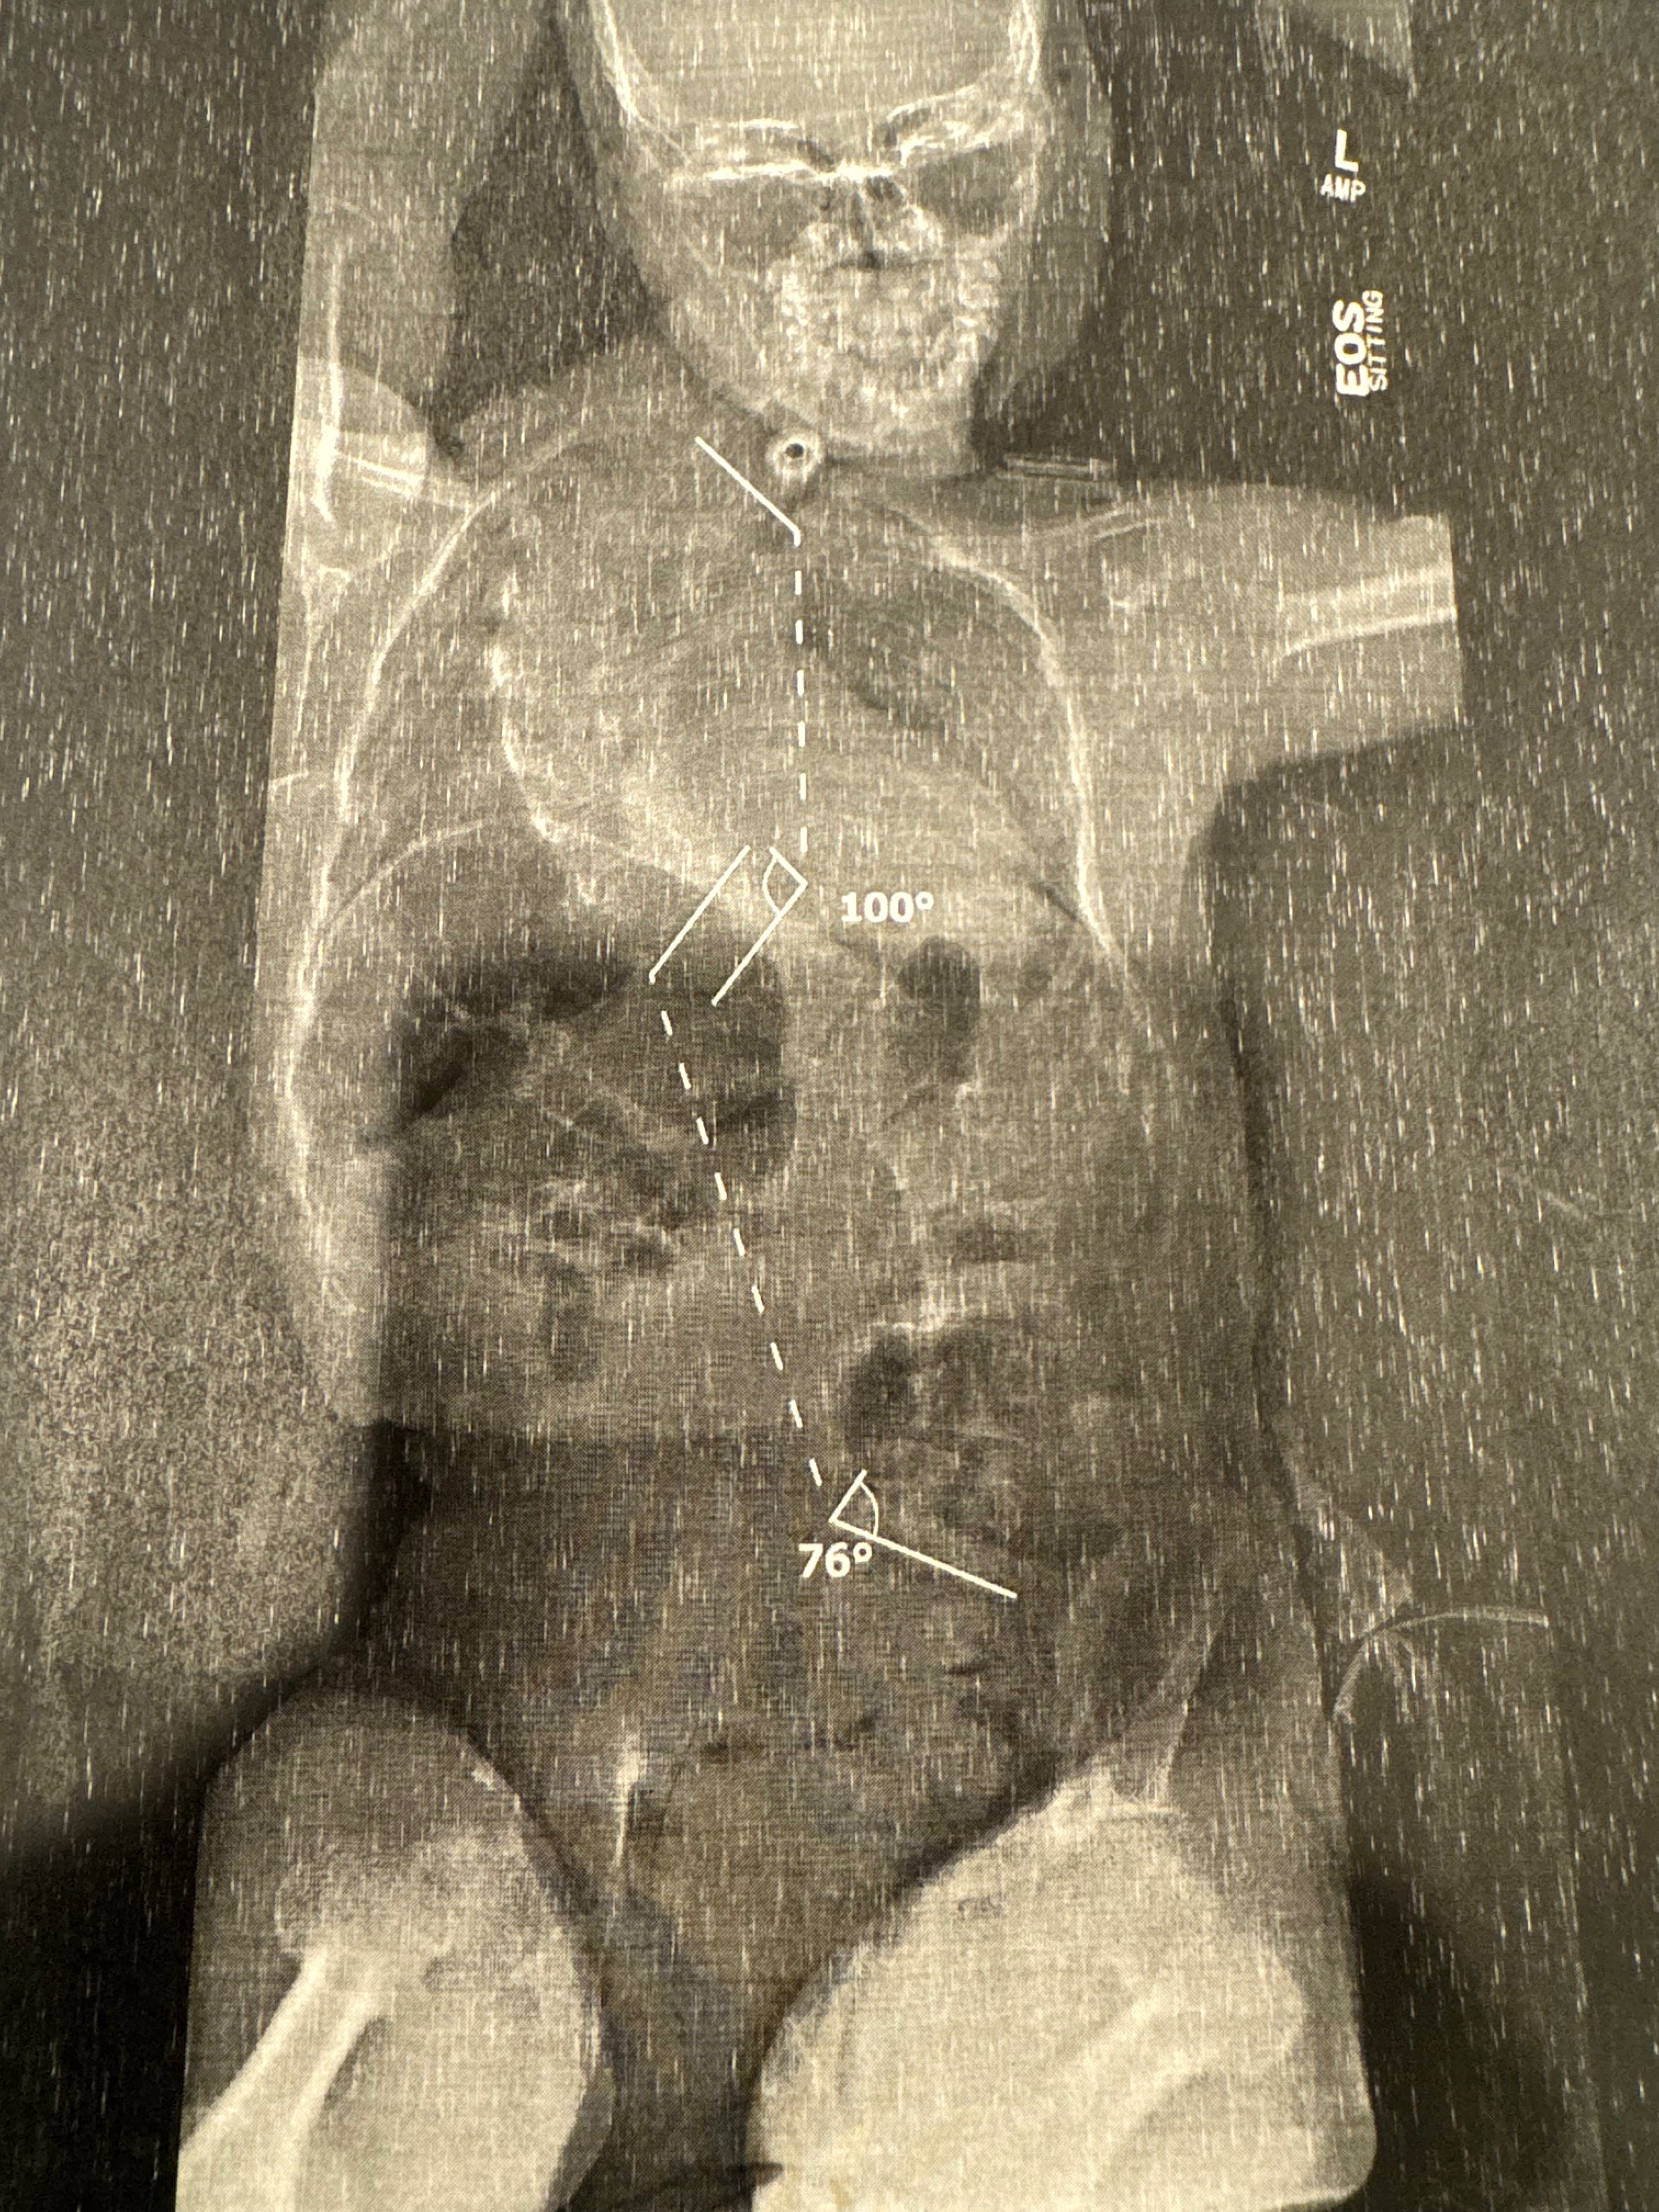

Hello my name is Jeremy James and I’m raising money for my son Jesse James who will be having spinal surgery to correct his scoliosis. My son is 14 yrs old and was born with complications, including Pierre Robin syndrome, Stickler syndrome, spinal bifida and cerebral palsy, he has a g-tube for his feeding and has never ate anything by mouth, so your donations would really help my family out in this difficult situation, thank you.